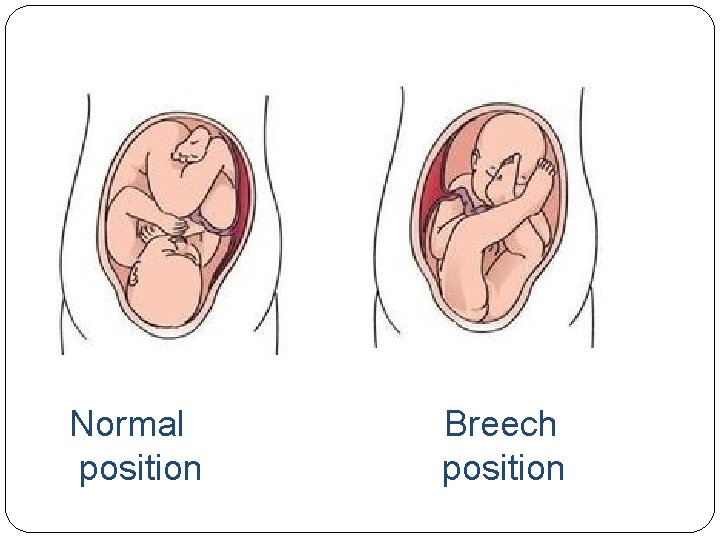

Normal Breech position

Risk Factors (The 4 F’s) �First born (small sized uterus ) � Female (relaxin hormone) � Family History � feet first (breech position)